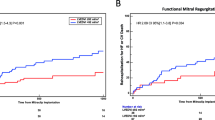

Multivariate Cox proportional-hazard regression analysis with the logistic EuroSCORE ≥40% (categorical variable) revealed the logistic EuroSCORE ≥40% as an independent predictor of a lower overall long-term survival (hazard ratio 16.69 (95% CI 4.23-65.84), Wald χ2 16.16, P < 0.001). The χ2 goodness-of-fit test (log likelihood ratio test) was significant, indicating that this multivariate model is a good fit (χ2 = 26.56, df = 1, P < 0.001). The influence of a logistic EuroSCORE ≥40% on overall long-term survival is shown in a Kaplan-Meier survival curve (Figure 2A). Patients with a logistic EuroSCORE ≥40% had a significantly lower mean overall long-term survival (1.1 ± 0.6 years) compared to patients with a logistic EuroSCORE <40% (14.5 ± 1.4 years, P < 0.001).

Multivariate Cox proportional-hazard regression analysis with the logistic EuroSCORE ≥25% (categorical variable) revealed the logistic EuroSCORE ≥25% as an independent predictor of a lower overall long-term survival (hazard ratio 4.31 (95% CI 1.67-11.14), Wald χ2 9.12, P = 0.003). The χ2 goodness-of-fit test (log likelihood ratio test) was significant, indicating that this multivariate model is a good fit (χ2 = 10.64, df = 1, P = 0.001). The influence of an EuroSCORE II ≥25% on overall long-term survival is shown in a Kaplan-Meier survival curve (Figure 2B). Patients with an EuroSCORE II ≥25% had a significantly lower mean overall long-term survival (2.5 ± 1.2 years) compared to patients with an EuroSCORE II <25% (14.1 ± 1.5 years, P < 0.001).

Kaplan-Meier actuarial overall long-term survival after mitral valve surgery for post-MI PMR. A: No preoperative inotropic drug support vs. preoperative inotropic drug support. B: Mitral valve replacement with (partial or complete) preservation of the subvalvular apparatus or mitral valve repair vs. mitral valve replacement without (partial or complete) preservation of the subvalvular apparatus. C: Mitral valve replacement with (partial or complete) preservation of the subvalvular apparatus vs. mitral valve replacement without (partial or complete) preservation of the subvalvular apparatus. MVP = mitral valve plasty/repair; MVR = mitral valve replacement; SA = subvalvular apparatus; Pts = patients; + = censored.